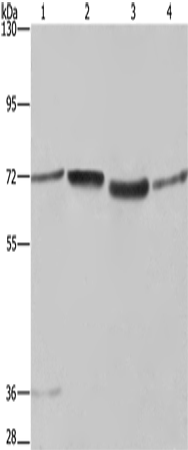

分类: 科研抗体货号: P11855别名: IMPD; RP10; IMPD1; LCA11; sWSS2608应用: WB,IHC反应种属: Human, Mouse, Rat